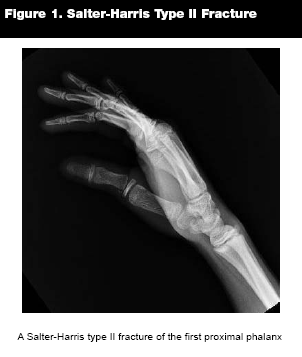

Type II. Salter-Harris II fractures are the most common type, accounting for 75% of all physeal fractures.2,11 (See Figure 1.) They extend through the physis and metaphysis. The segment of metaphyseal bone is referred to as the "Thurston-Holland" fragment or sign.2 The germinal layer is not involved; therefore, growth disturbances are rare. These injuries may also require treatment with gentle reduction by a subspecialist if there is displacement, and immobilization along with outpatient follow-up. Excessive closed manipulation can lead to an increase in the amount of physeal damage, increasing the risk for growth plate arrest.5 A perfect reduction is not an absolute requirement, as the younger the child, the greater capacity for bone remodeling.